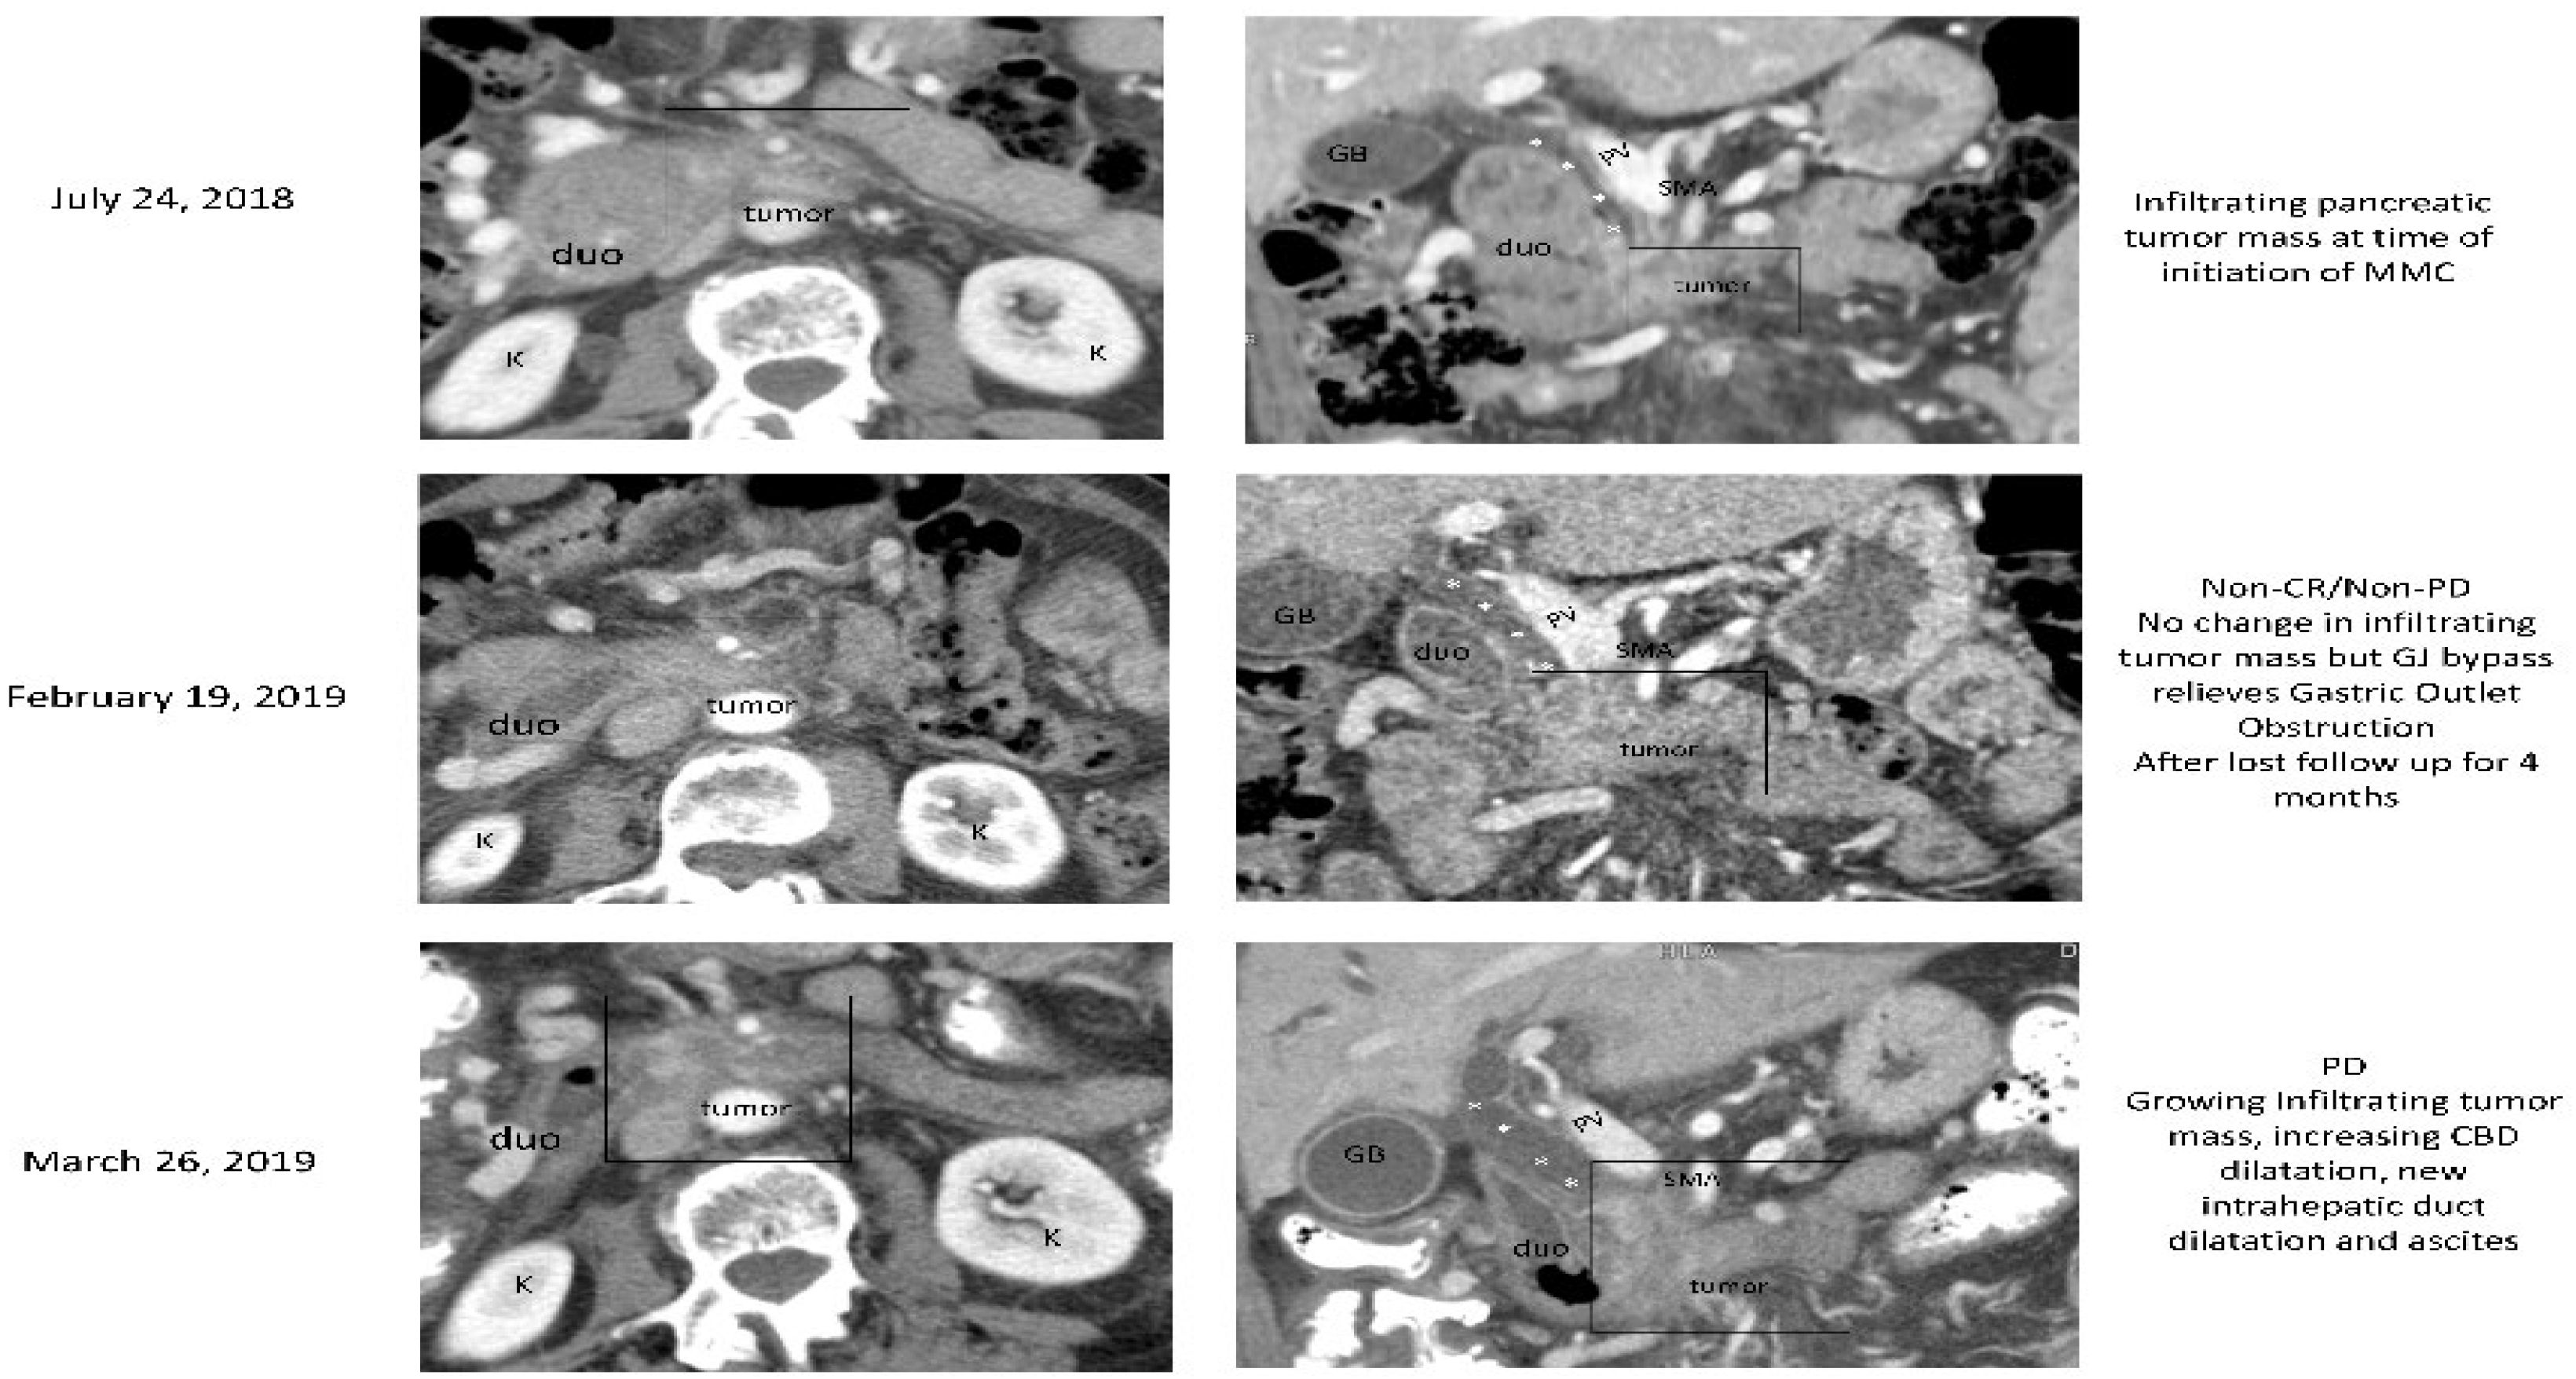

3.2.2. Case (2)